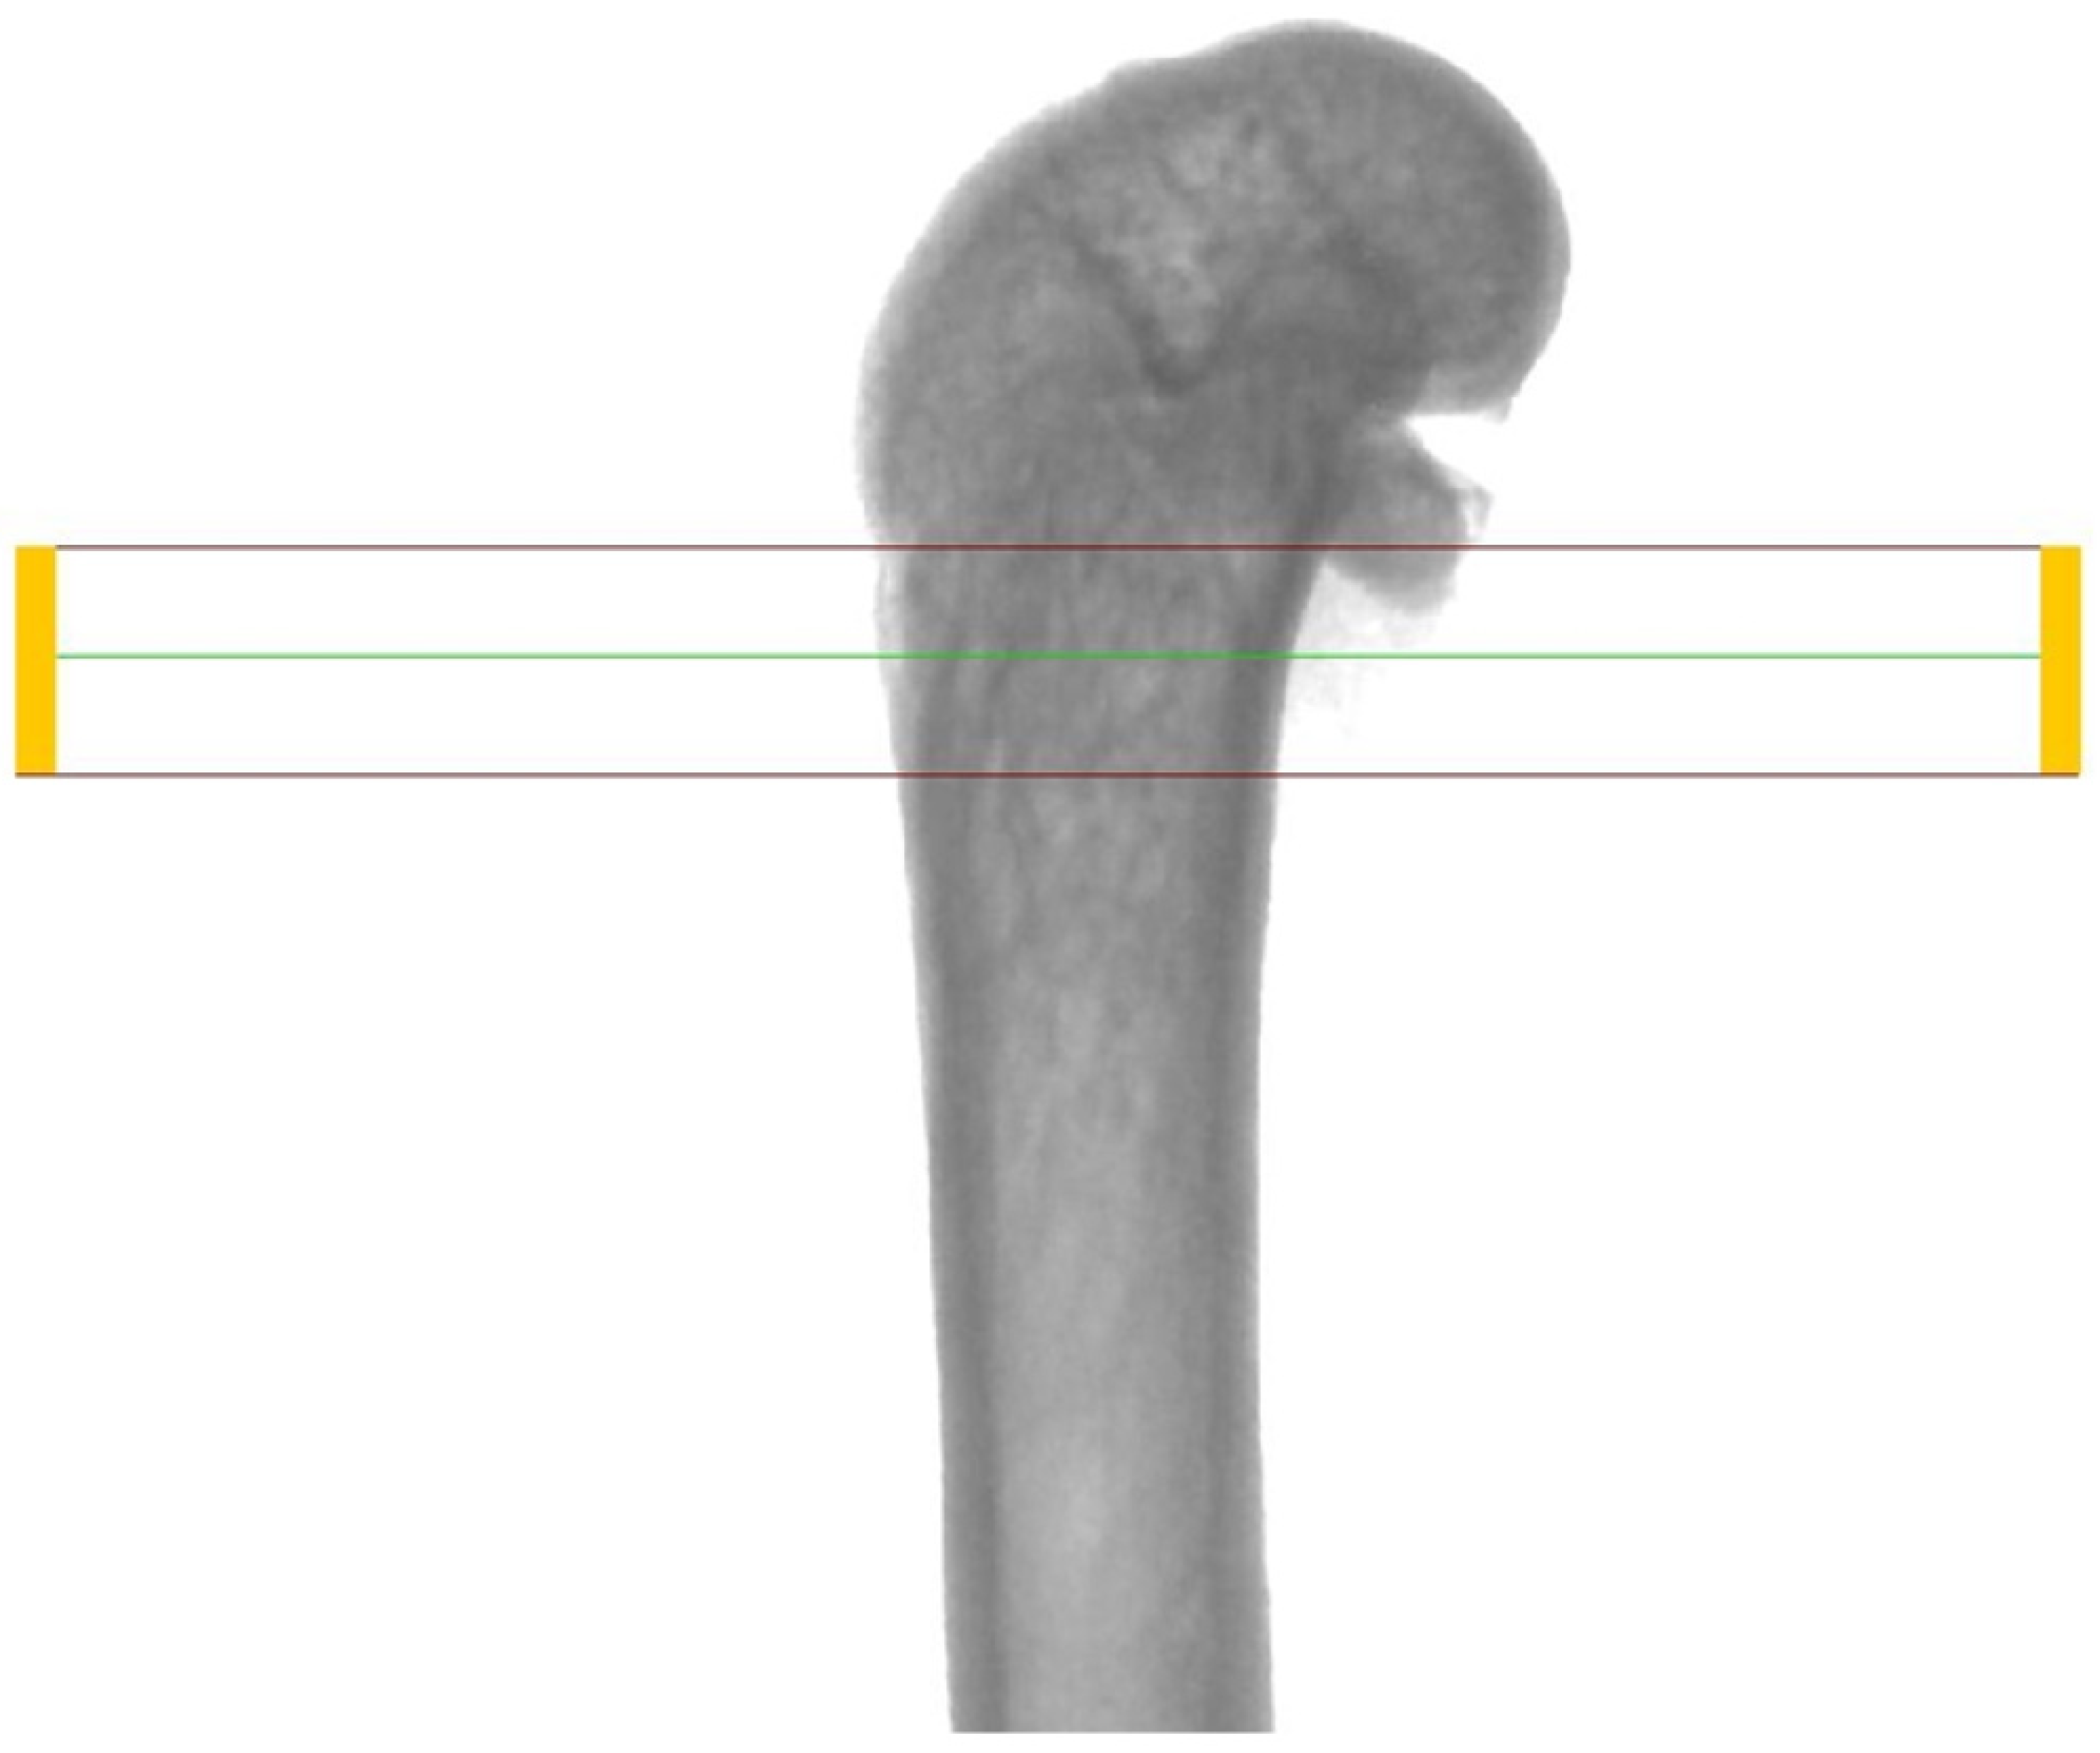

2.2. Micro-CT Analysis